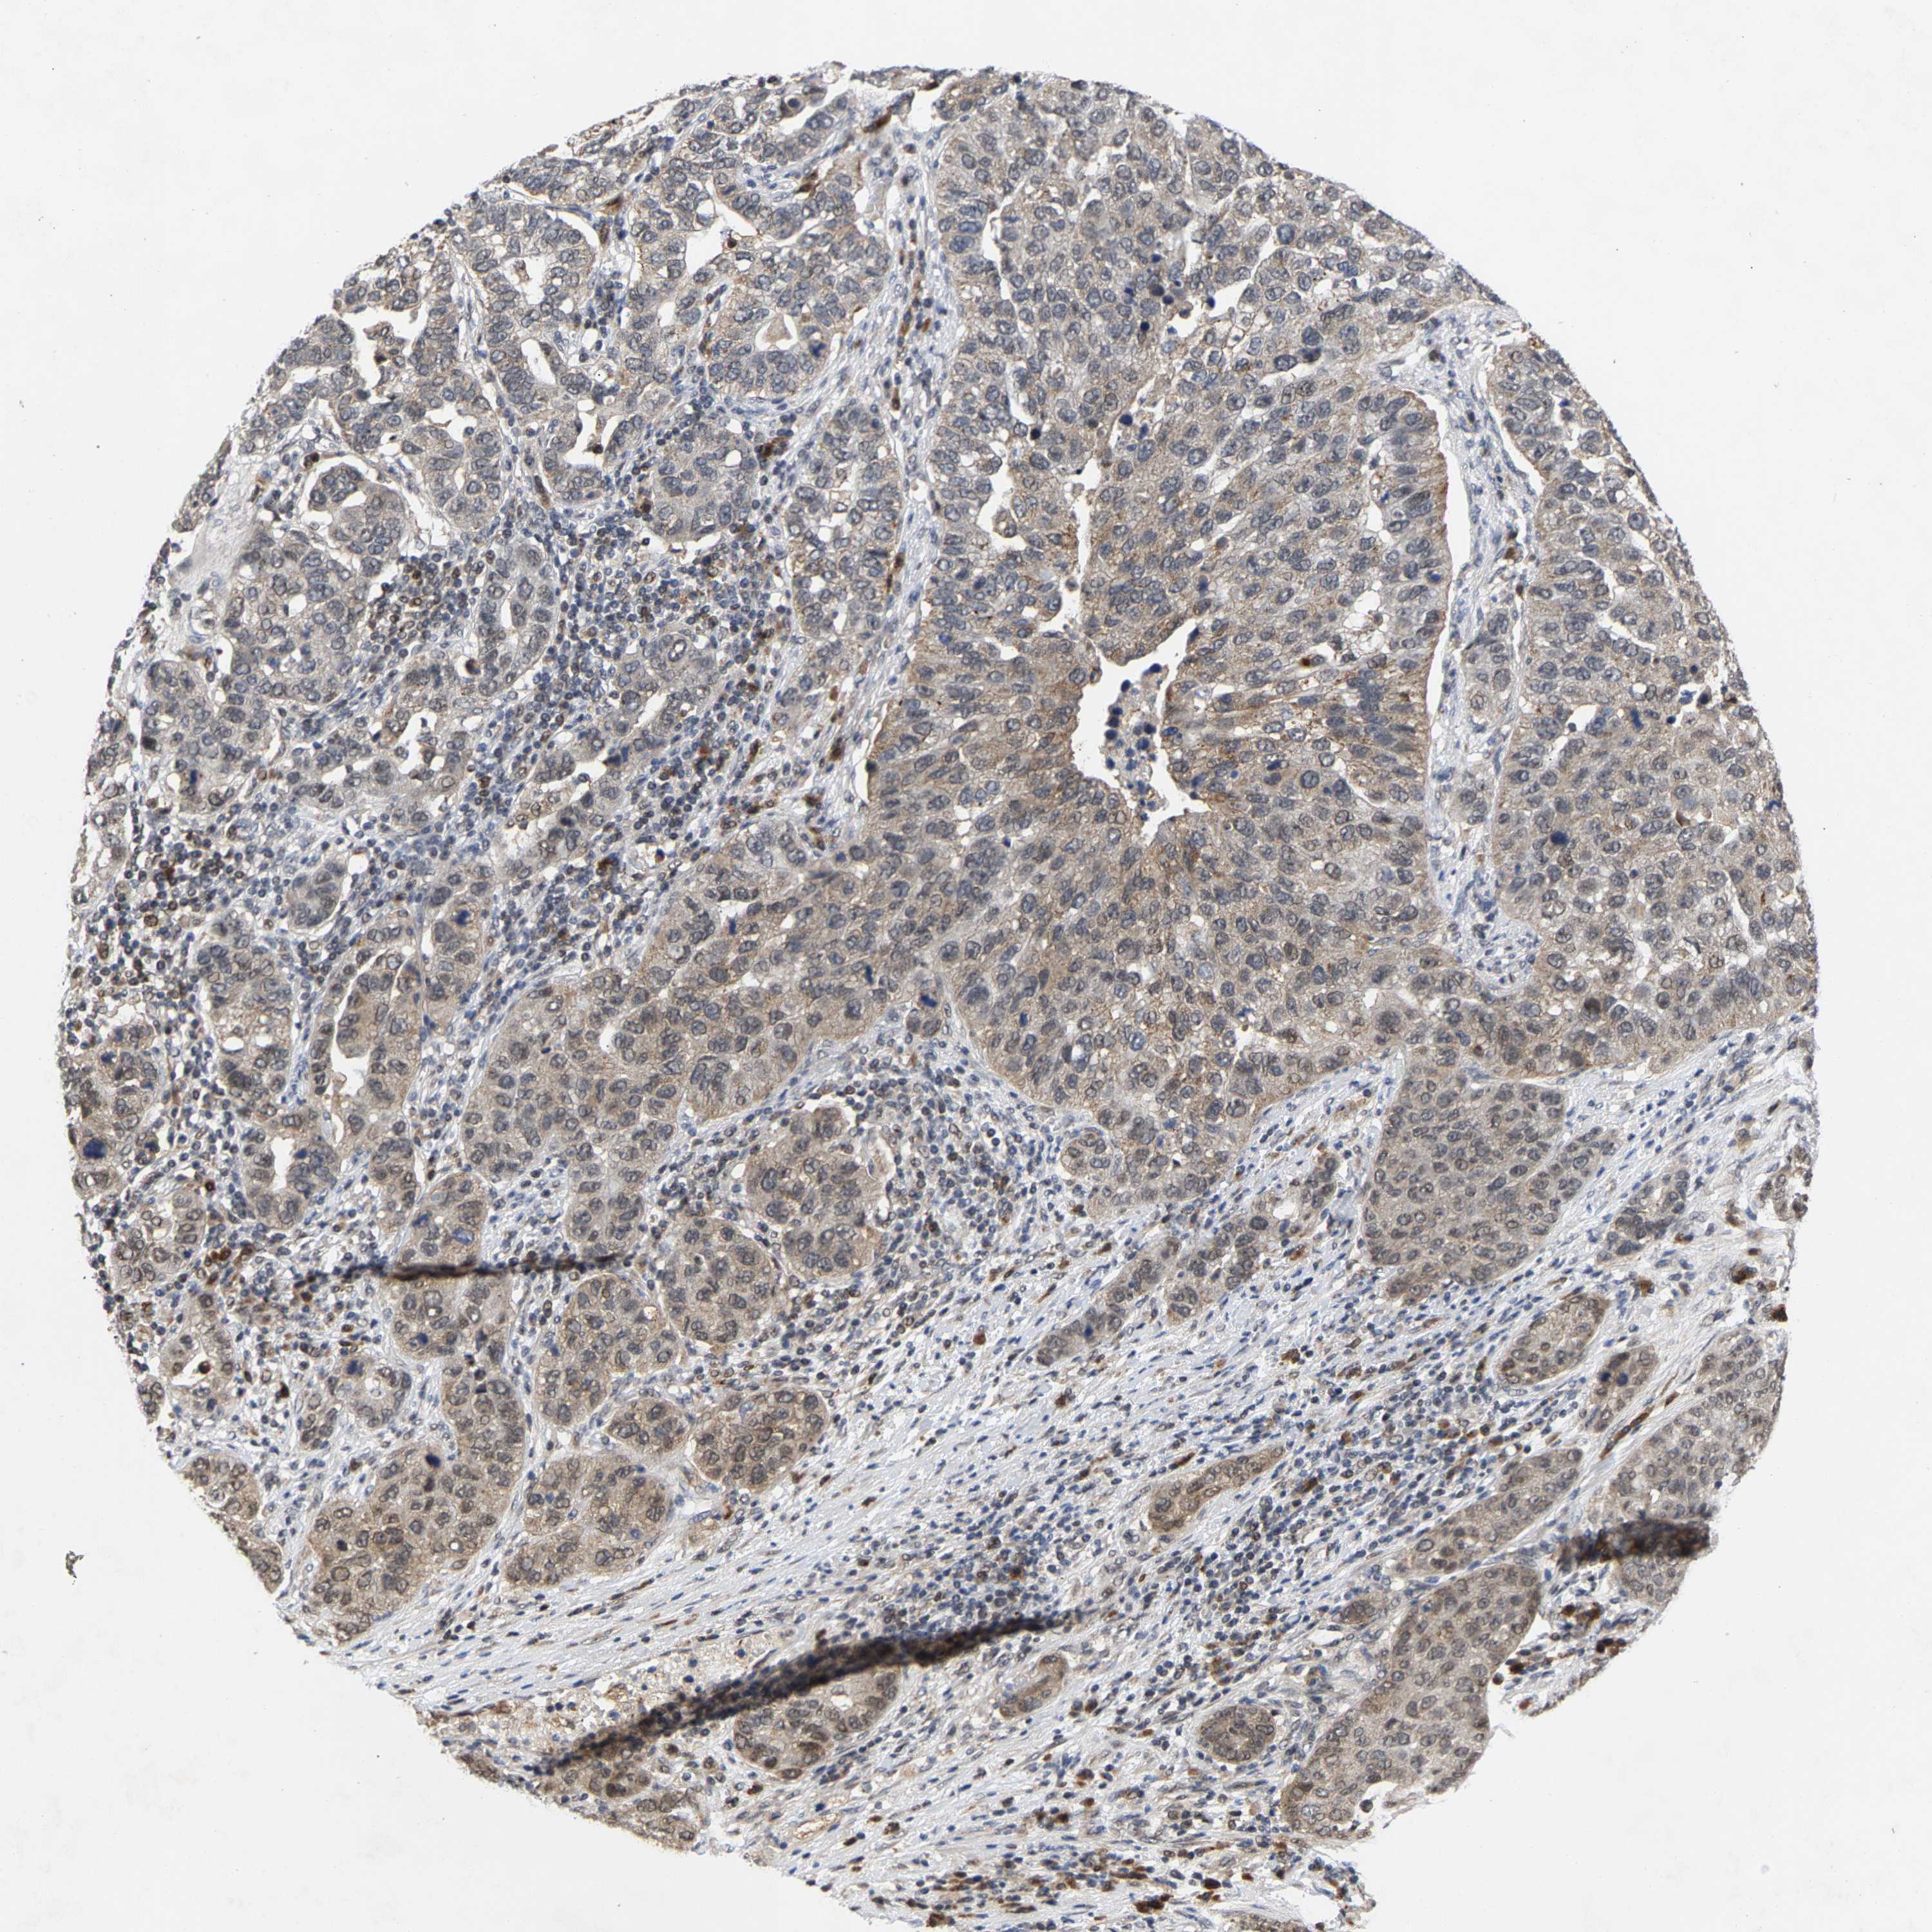

PANCREATIC CANCER - Protein expressioni

A mouse-over function shows sample information and annotation data. Click on an image to view it in a full screen mode. Samples can be filtered based on level of antibody staining by selecting one or several of the following categories: high, medium, low and not detected. The assay and annotation is described here.

Note that samples used for immunohistochemistry by the Human Protein Atlas do not correspond to samples in the TCGA dataset.

Antibody stainingi

Antibody staining in the annotated cell types in the current human tissue is reported as not detected, low, medium, or high, based on conventional immunohistochemistry profiling in selected tissues. This score is based on the combination of the staining intensity and fraction of stained cells.

Each image is clickable and will lead to virtual microscopy that enables deeper exploration of all samples and also displays staining intensity scores, fraction scores and subcellular localization as well as patient and tissue information for each sample.

Antibody HPA020430

Antibody CAB020767

Staining

High

Medium

Low

Not detected

Intensity

Strong

Moderate

Weak

Negative

Quantity

>75%

75%-25%

<25%

None

Location

Nuclear

Cytoplasmic/membranous

Cytoplasmic/membranous,nuclear

Adenocarcinoma, NOS